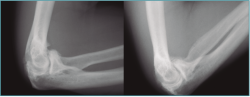

Las pruebas de imagen más útiles en este contexto son la radiografía simple (Figura 3) y la tomografía computarizada (TC) (Figuras 4 y 5), que evalúan la congruencia de las superficies articulares, la presencia de osteofitos u osificación ectópica, o alteraciones de la alineación ósea. Además, se evaluará la consolidación de fracturas previas, si es el caso, o la posible implicación del material de osteosíntesis en la falta de movilidad (si está correctamente situado, no tiene por qué interferir con la movilidad del codo)(6).

Figura 3. Radiografía de paciente con rigidez de codo con presencia de material de osteosíntesis a nivel de cúbito proximal y protésico a nivel de radio proximal.